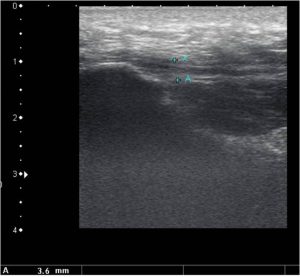

• Normal ultrasound appearance of the plantar fascia – homogenous linear pattern of the tissue ranging in thickness from 3-4mm

• Ultrasound appearance of plantar fasciitis – heterogenous linear pattern of the tissue with mixed echogenicity ranging in thickness from 6-8mm

note the heterogenous linear pattern of the tissue with mixed echogenicity. Plantar fascia is very thick  – heel spur present but this is of no clinical significance